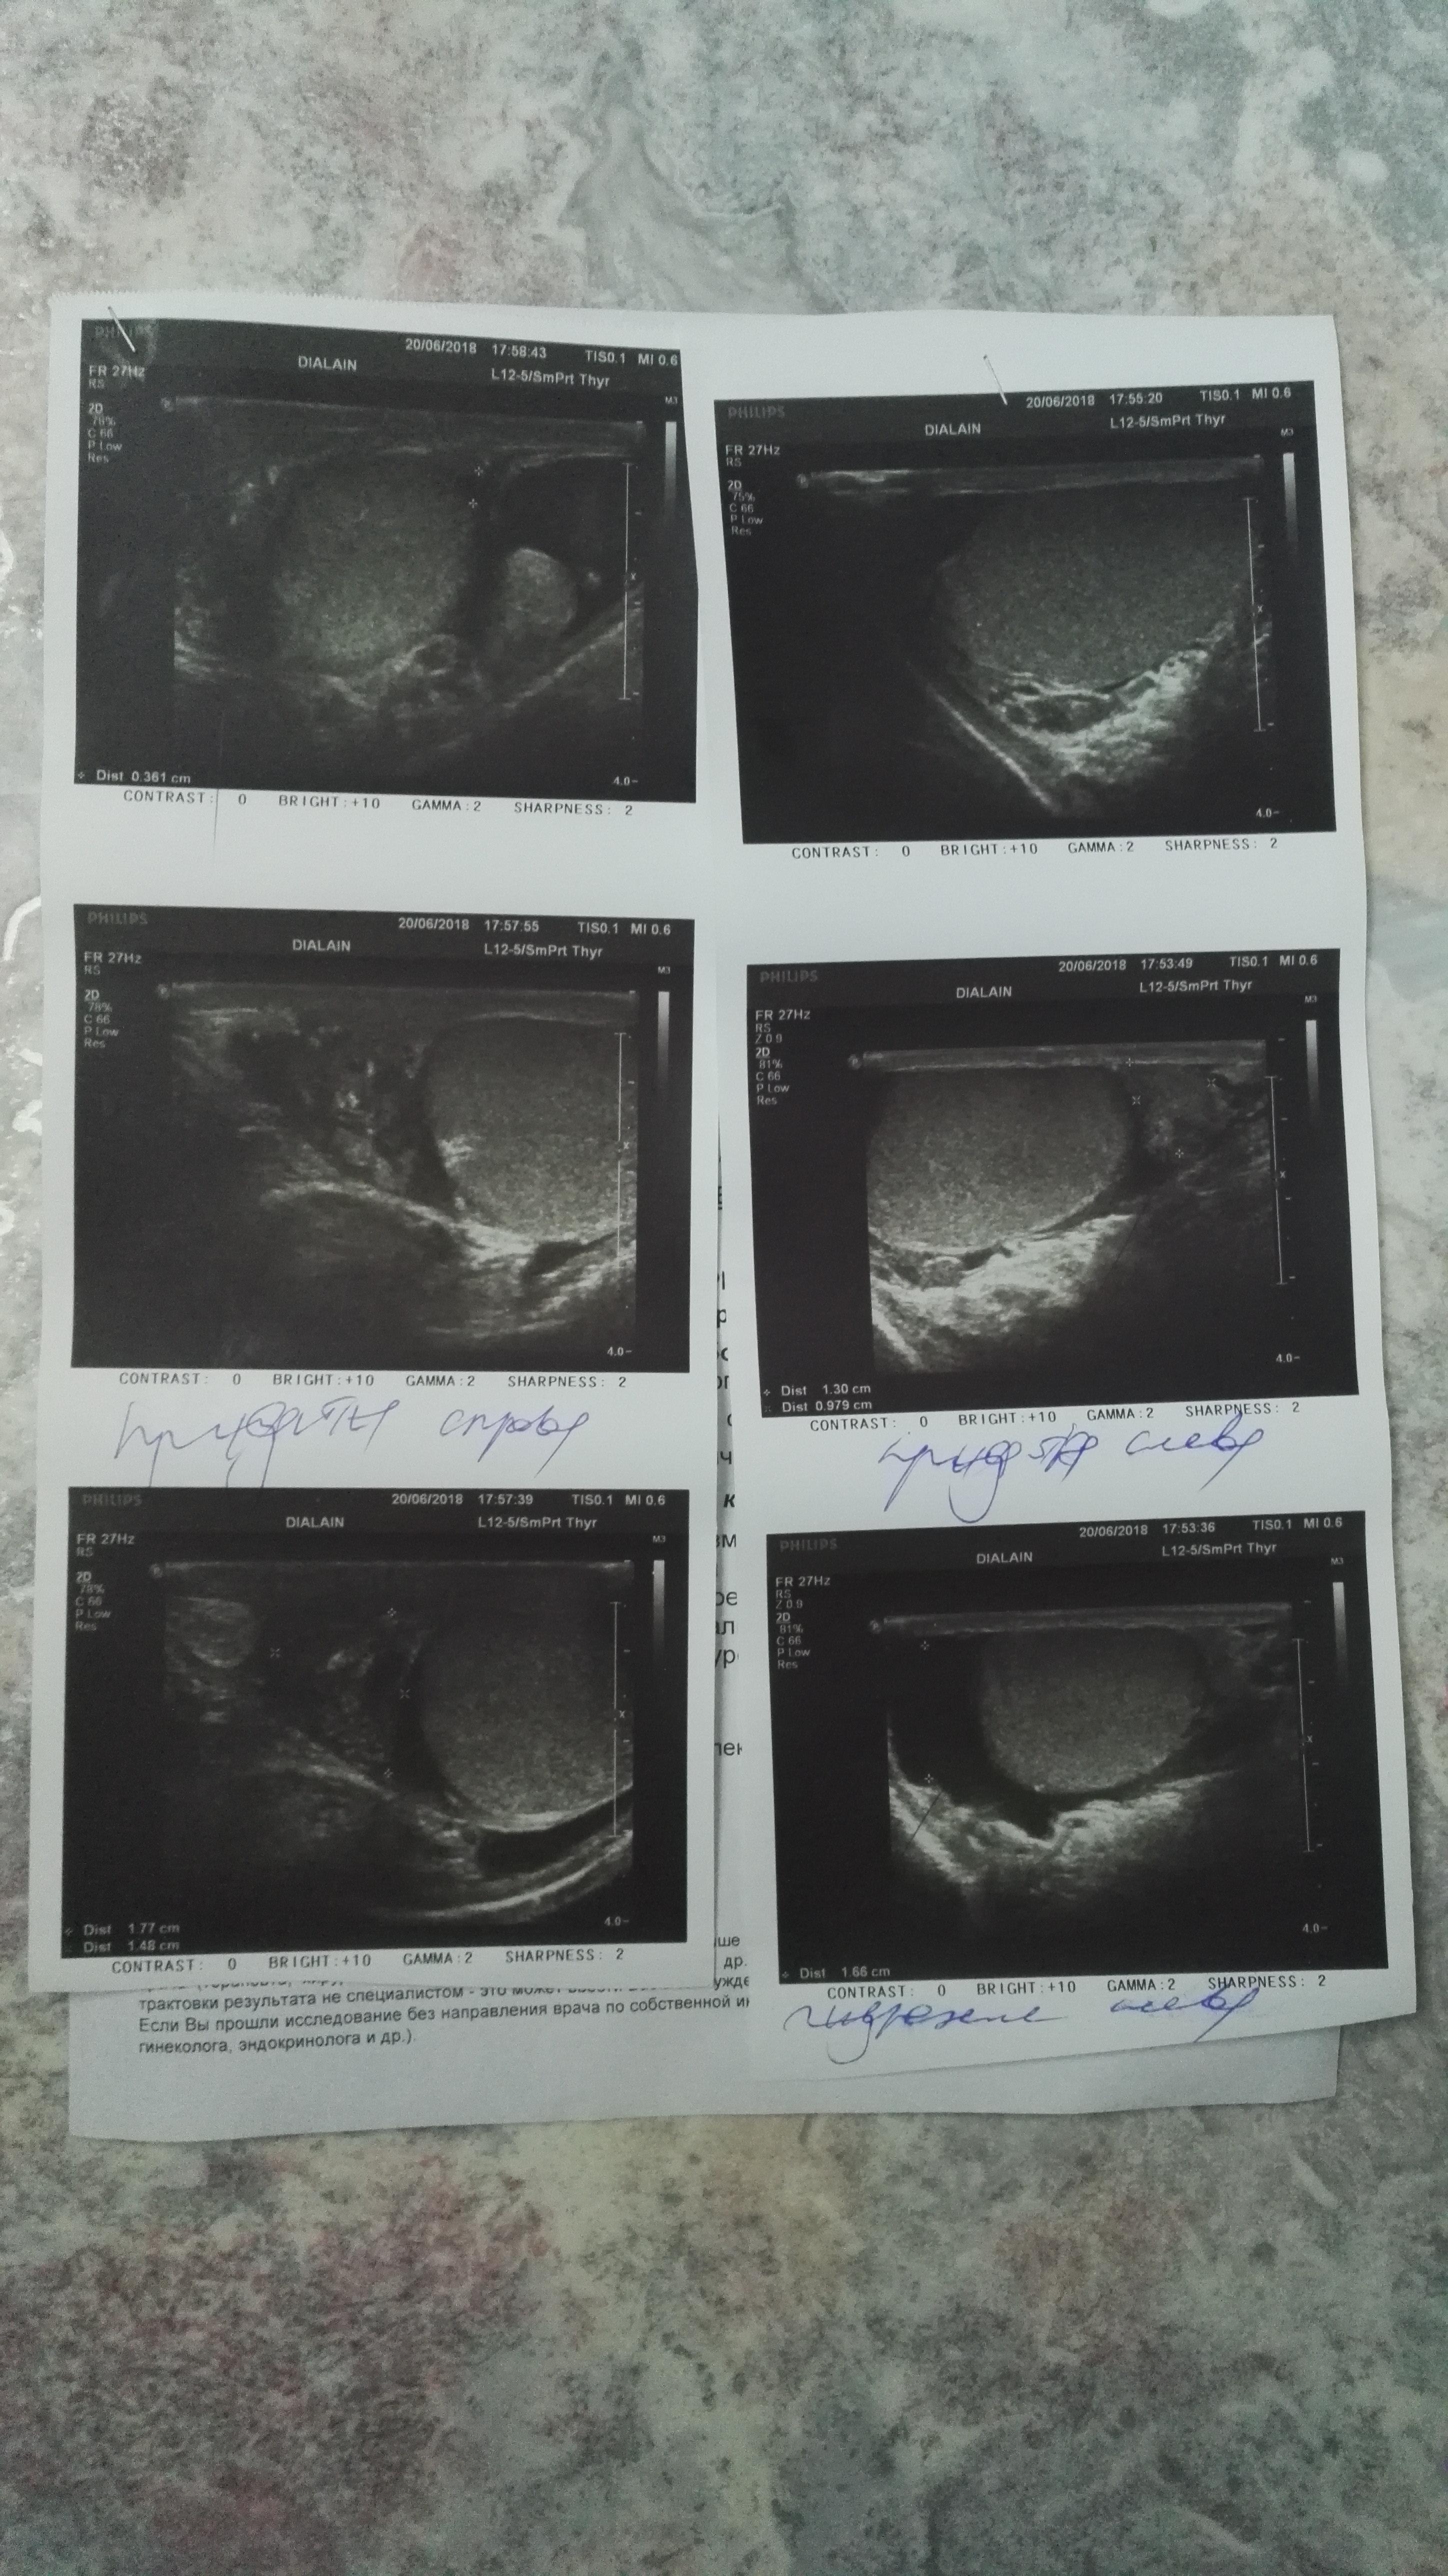

Здравствуйте. 3мая сделали операцию на водянку яичка слева, в ноцк операции почувствовал резкие боли справа. Врачи не понимают в чем дело а я бегаю и показываю УЗИ . Изменился стул, какие то непонятные покалывания по телу, температуры нет.

Нужен осмотр - заочно сложно определить причину болей. По УЗИ - киста придатка яичка, но она не вызывает острые боли. Изменение стула и покалывания по телу - не относятся к урологическим проблемам и не связаны ни с водянкой, ни с кистой. С уважением.